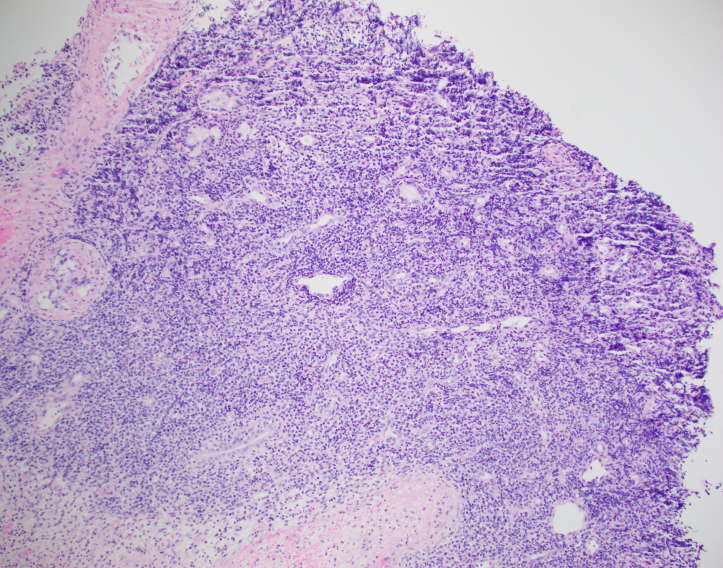

The biopsy shows nasal mucosa with a dense submucosal lymphoid infiltrate and large areas of necrosis. The lymphocytes are somewhat pleomorphic, medium to large in size with irregular nuclear contours, vesicular chromatin and inconspicuous nucleoli. There are scattered mitoses and apoptotic cells.

Microscopically, the involved sites generally have widespread mucosal destruction. There is an angioentric and angiodestructive growth pattern that results in extensive necrosis. Another important diagnostic consideration is the very strong association with EBV. EBV is present in a clonal episomal form. This means that the infection occurs prior to and likely plays a pathogenic role in the development of NK/T cell lymphomas. 3